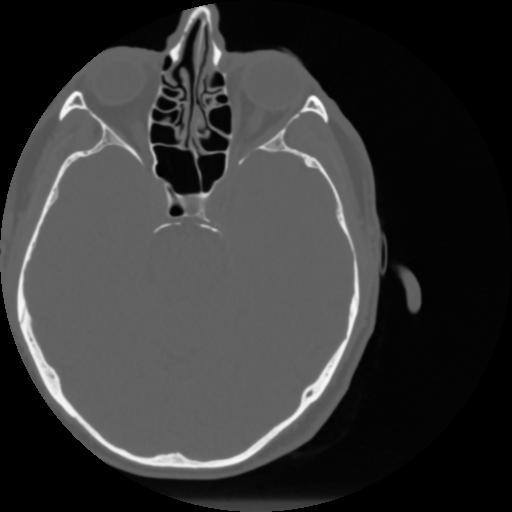

4 CEREBRO,,Vol,0.5,CEREBRO,,